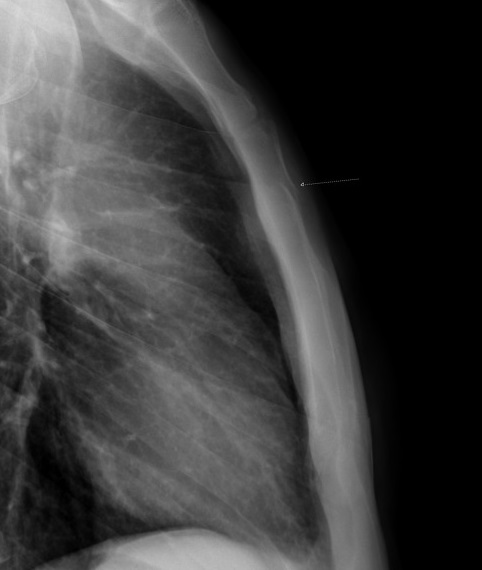

Aspect radiologique du

fracture des côtes 7th , 8th droit . Il est

difficile d'evaluer de la lesion et de la cite de

fracture sur le plain film de face PA |

Même cas en position OAD , on peut

detecter la fracture du co6te 7, 8th droit . |